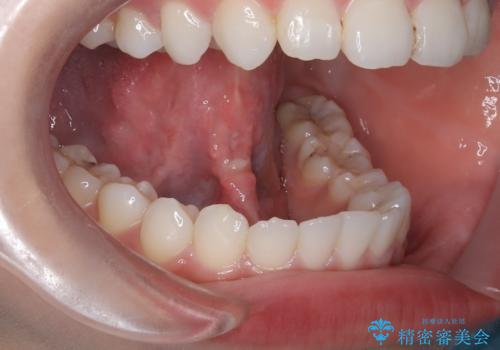

- 20代女性

- 1ヶ月

- 2-5回

- 3.3万円費用は治療当時の料金となります